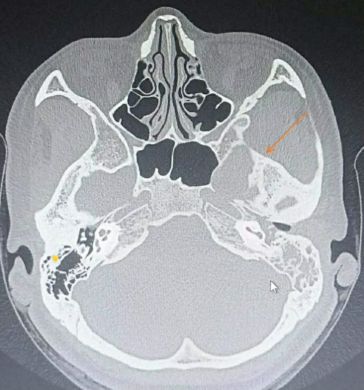

术前CT显示肿瘤和扩大的卵圆孔

结合术前颞骨CT薄层扫描+增强核磁,我们应该选择入路?

继续磨除骨质显示圆孔,卵圆孔以及V2-V3